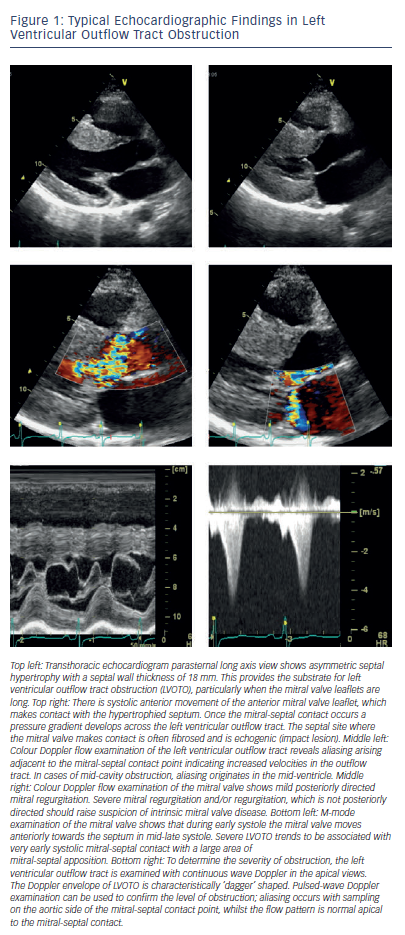

LVOTO is caused by the SAM of the mitral valve. In systole, the anterior mitral valve leaflet moves into the left ventricular outflow tract (LVOT), which is already narrowed by the hypertrophied septum creating a physical barrier, which impedes the flow of blood from the ventricle to the aorta during systole (see Figure 1).2,3 Contact of the mitral valve leaflets to the septum is termed ‘complete’ SAM, and lesser forms of SAM where there is no contact are termed ‘incomplete’. SAM of the mitral valve leaflets is often associated with varying degrees of mitral regurgitation since the two mitral valve leaflets are pulled apart during SAM, creating an orifice through which retrograde, posteriorly-directed flow in the left atrium can occur. Consequently, conditions which increase LVOTO also increase the severity of mitral regurgitation.3,29 LVOTO is also promoted by coincident abnormalities of the mitral valve leaflets. The leaflets (particularly the anterior leaflet) are frequently elongated and displaced anteriorly, with abnormal attachments to the papillary muscles and chordae.30,31 Early investigators attributed SAM of the mitral valve to suction forces (Venturi effect) caused by accelerating blood flow in LVOT during systole, drawing the mitral valve leaflets anteriorly into the outflow tract. However, SAM of the mitral valve commences in early systole when the Venturi effect is minimal, and this is therefore unlikely to be the sole explanation for LVOTO.32,33 The mechanism underlying LVOTO is probably multi-factorial, involving the interaction of abnormalities of papillary muscles, chordae, mitral leaflets and LVH, which culminate in abnormal flow forces that push and/or pull the mitral valve towards the outflow septum.33 Although LVOTO gradient is the most evident abnormality, the physiology of obstructive disease includes elevated left ventricular (LV) end-diastolic pressure, mitral regurgitation and a potential for abrupt changes in LVOTO magnitude (for example with postural change or sudden exertion); these abnormalities, as well as the increased LV afterload, may all contribute to symptoms.

A characteristic feature of LVOTO is that the severity of the obstruction is dynamic and subject to prevailing haemodynamic conditions. LVOTO is exacerbated by conditions causing reduced preload (e.g. Valsalva, squat to stand), reduced afterload (e.g. vasodilators) or positive inotropes.3 Notably, although LVOTO is most often seen in HCM, it may also occur in other conditions or physiological states and is not pathognomonic of HCM.34,35 In a smaller subgroup of HCM patients, obstruction can develop at the mid-left ventricular cavity. Mid-cavity obstruction is caused by the systolic apposition of hypertrophied mid-ventricular segments and/or papillary muscles creating a characteristic hour-glass appearance with a distinct apical cavity.36,37 This form of obstruction is often associated with apical aneurysm formation.36,37 Mid-cavity obstruction can exist in isolation (see Figure 2) or in conjunction with LVOTO. Even though ASA has been used in the treatment of mid-cavity obstruction,38,39 this is not routine practice and further discussion is beyond the scope of this review.